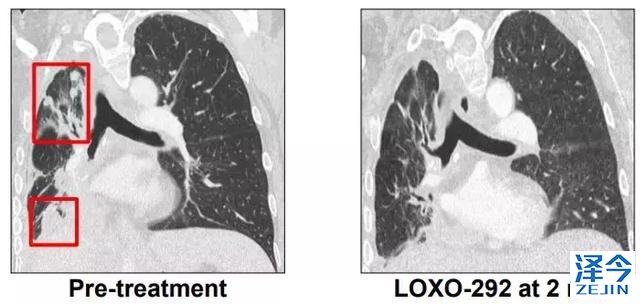

M女士走图无路的情况下接受了基因检测,发现了KIF5B-RET融合,开始接受600 mg BID靶向药 alectinib治疗(PR,7个月),由于脑转移进展增加至900mg BID,后脑转移症状严重,M女士接受了LOXO-292治疗,于是奇迹出现了,治疗两个月后,M女士肺部的病灶明显好转,脑部病灶几乎全部消失!

另一位52岁的肺癌患者,化疗耐药之后进行基因检测发现具有KIF5B-RET基因融合,使用LOXO292 4周之后肿瘤显著缩小。